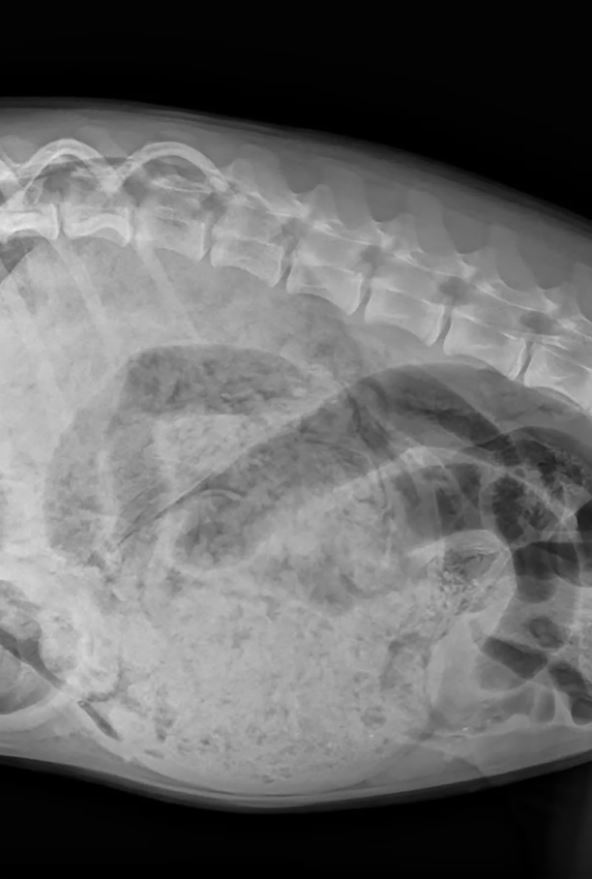

redgen snimak psa Lune koja je pojela čarape

"Ono što smo pronašli bilo je neverovatno", napisala je bolnica, uz rendgenske snimke Luninog stomaka punog odeće, kao i fotografije njenog oporavka i snimak veterinarke, dr Dženi, koja pozira sa svim stvarima koje su pronađene u njenom stomaku - uključujući "24 čarape, dve gumice za kosu, jedan uložak za obuću, jedan mali kombinezon (iz njenog creva!) i razne komade tkanine."